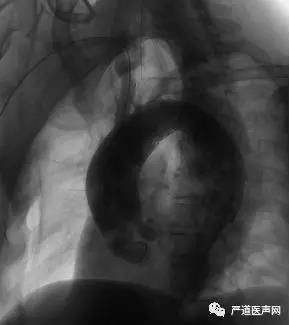

释放成功后再送入猪尾导管于升主动脉复查造影,结果提示支架贴壁良好,主动脉隔绝良好,头臂干及弓上血管血流通畅,未见明显内漏(如下图)。